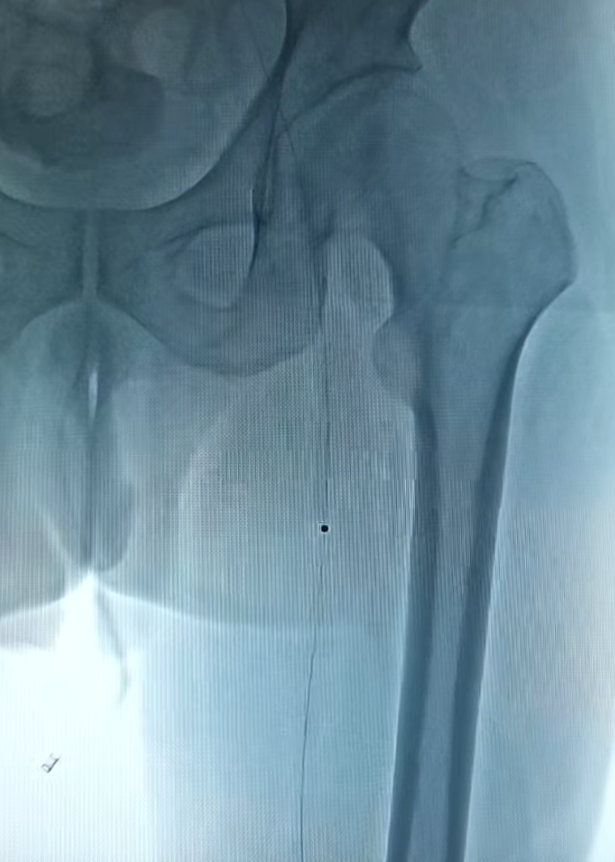

IVUS引导下的准分子激光斑块消蚀术中影像

手术中,血管外科团队首先将纤细的IVUS导管送入血管闭塞段。IVUS如同深入血管内部的“高清雷达”,实时生成血管横截面的高清图像,清晰显示闭塞长度、斑块性质及血管真腔位置,为术者规划个体化治疗路径提供了精准依据。

随后,团队启动“准分子激光斑块消蚀系统”。在IVUS明确病变性质后,激光导管被精准送达目标位置。它发射特定波长的脉冲激光,能以“微观爆破”方式高效、安全地将硬化斑块甚至顽固钙化组织气化消蚀为微小微粒,从而为后续治疗开辟出通畅通道,这一技术尤其适用于导丝虽能通过但球囊无法扩张的坚硬病变。